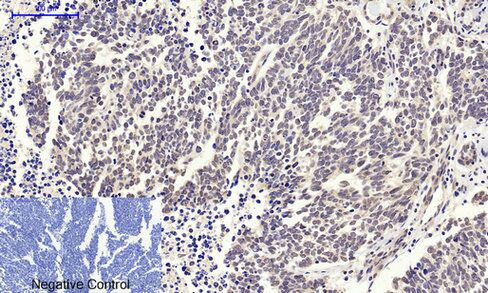

Immunohistochemical analysis of paraffin-embedded RAT testis tissue using c-Myc Polyclonal Antibody.